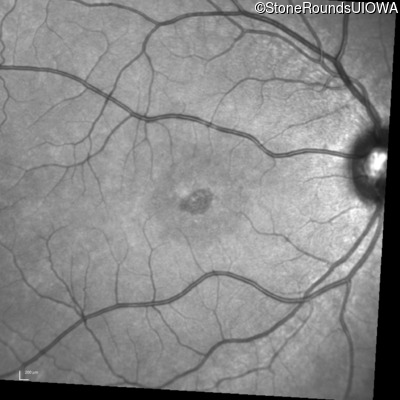

Infrared Fundus Photograph - Right - 20/50 -2

Exemplar

Infrared Fundus Photograph - Left - 20/50 -1